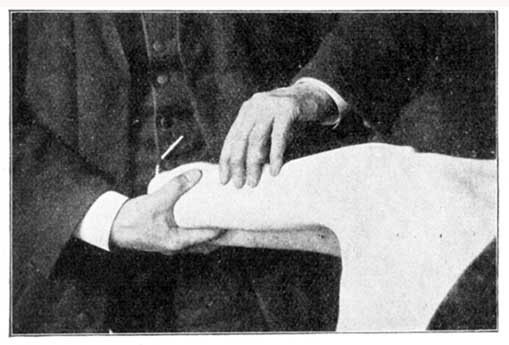

Ankle, Twisted or Crushed.—Place the foot as soon as possible in warm water, as hot as can comfortably be borne; keep it there until free from pain, or for an hour, or even more if necessary. If the flesh be torn, dress with cloths wrung out of vinegar or weak acetic acid before placing in the water.

When the bath has done its work, and the limb comes out of the water alarmingly swollen, good and skilful bandaging will do excellent work. If you have at hand an old shirt, or some such thing, tear it into strips about three inches wide, till you have as much material as will swathe the whole limb from behind the toes up to the top of the thigh. This need not be all in one piece, but only so that you may apply it in such a way as to bring a very gentle pressure on the whole surface of the injured limb. It is important that the bandaging should be comfortable. The way in which bandaging is sometimes done is cruel in the extreme. Cases that are a disgrace to humanity are constantly coming under our notice, in which limbs are lost for life by the treatment they receive in this respect. Skilful surgeons do it in the most gentle manner; they even swathe the limbs in soft loose cotton before they apply the bandages, so that a perfectly equal and comforting pressure may be secured. Lay the limb to rest, well and softly supported in a horizontal position. When the swelling falls, gently tighten the bandage from time to time as required. Each time the bandages are removed for this purpose, sponge the limb with warm vinegar or weak acetic acid (see). When the swelling subsides, the ankle may be put again in the hot bath for half-an-hour, and then, if any bones be broken, is the time for setting them right. The ankle will probably turn black. If so, do not apply leeches, but allow the black blood to be absorbed by natural process.

A twisted or bruised wrist or hand is to be treated in the same way. The swelling may also be removed by gentle rubbing upwards along the limb, so as to help the blood in its course.